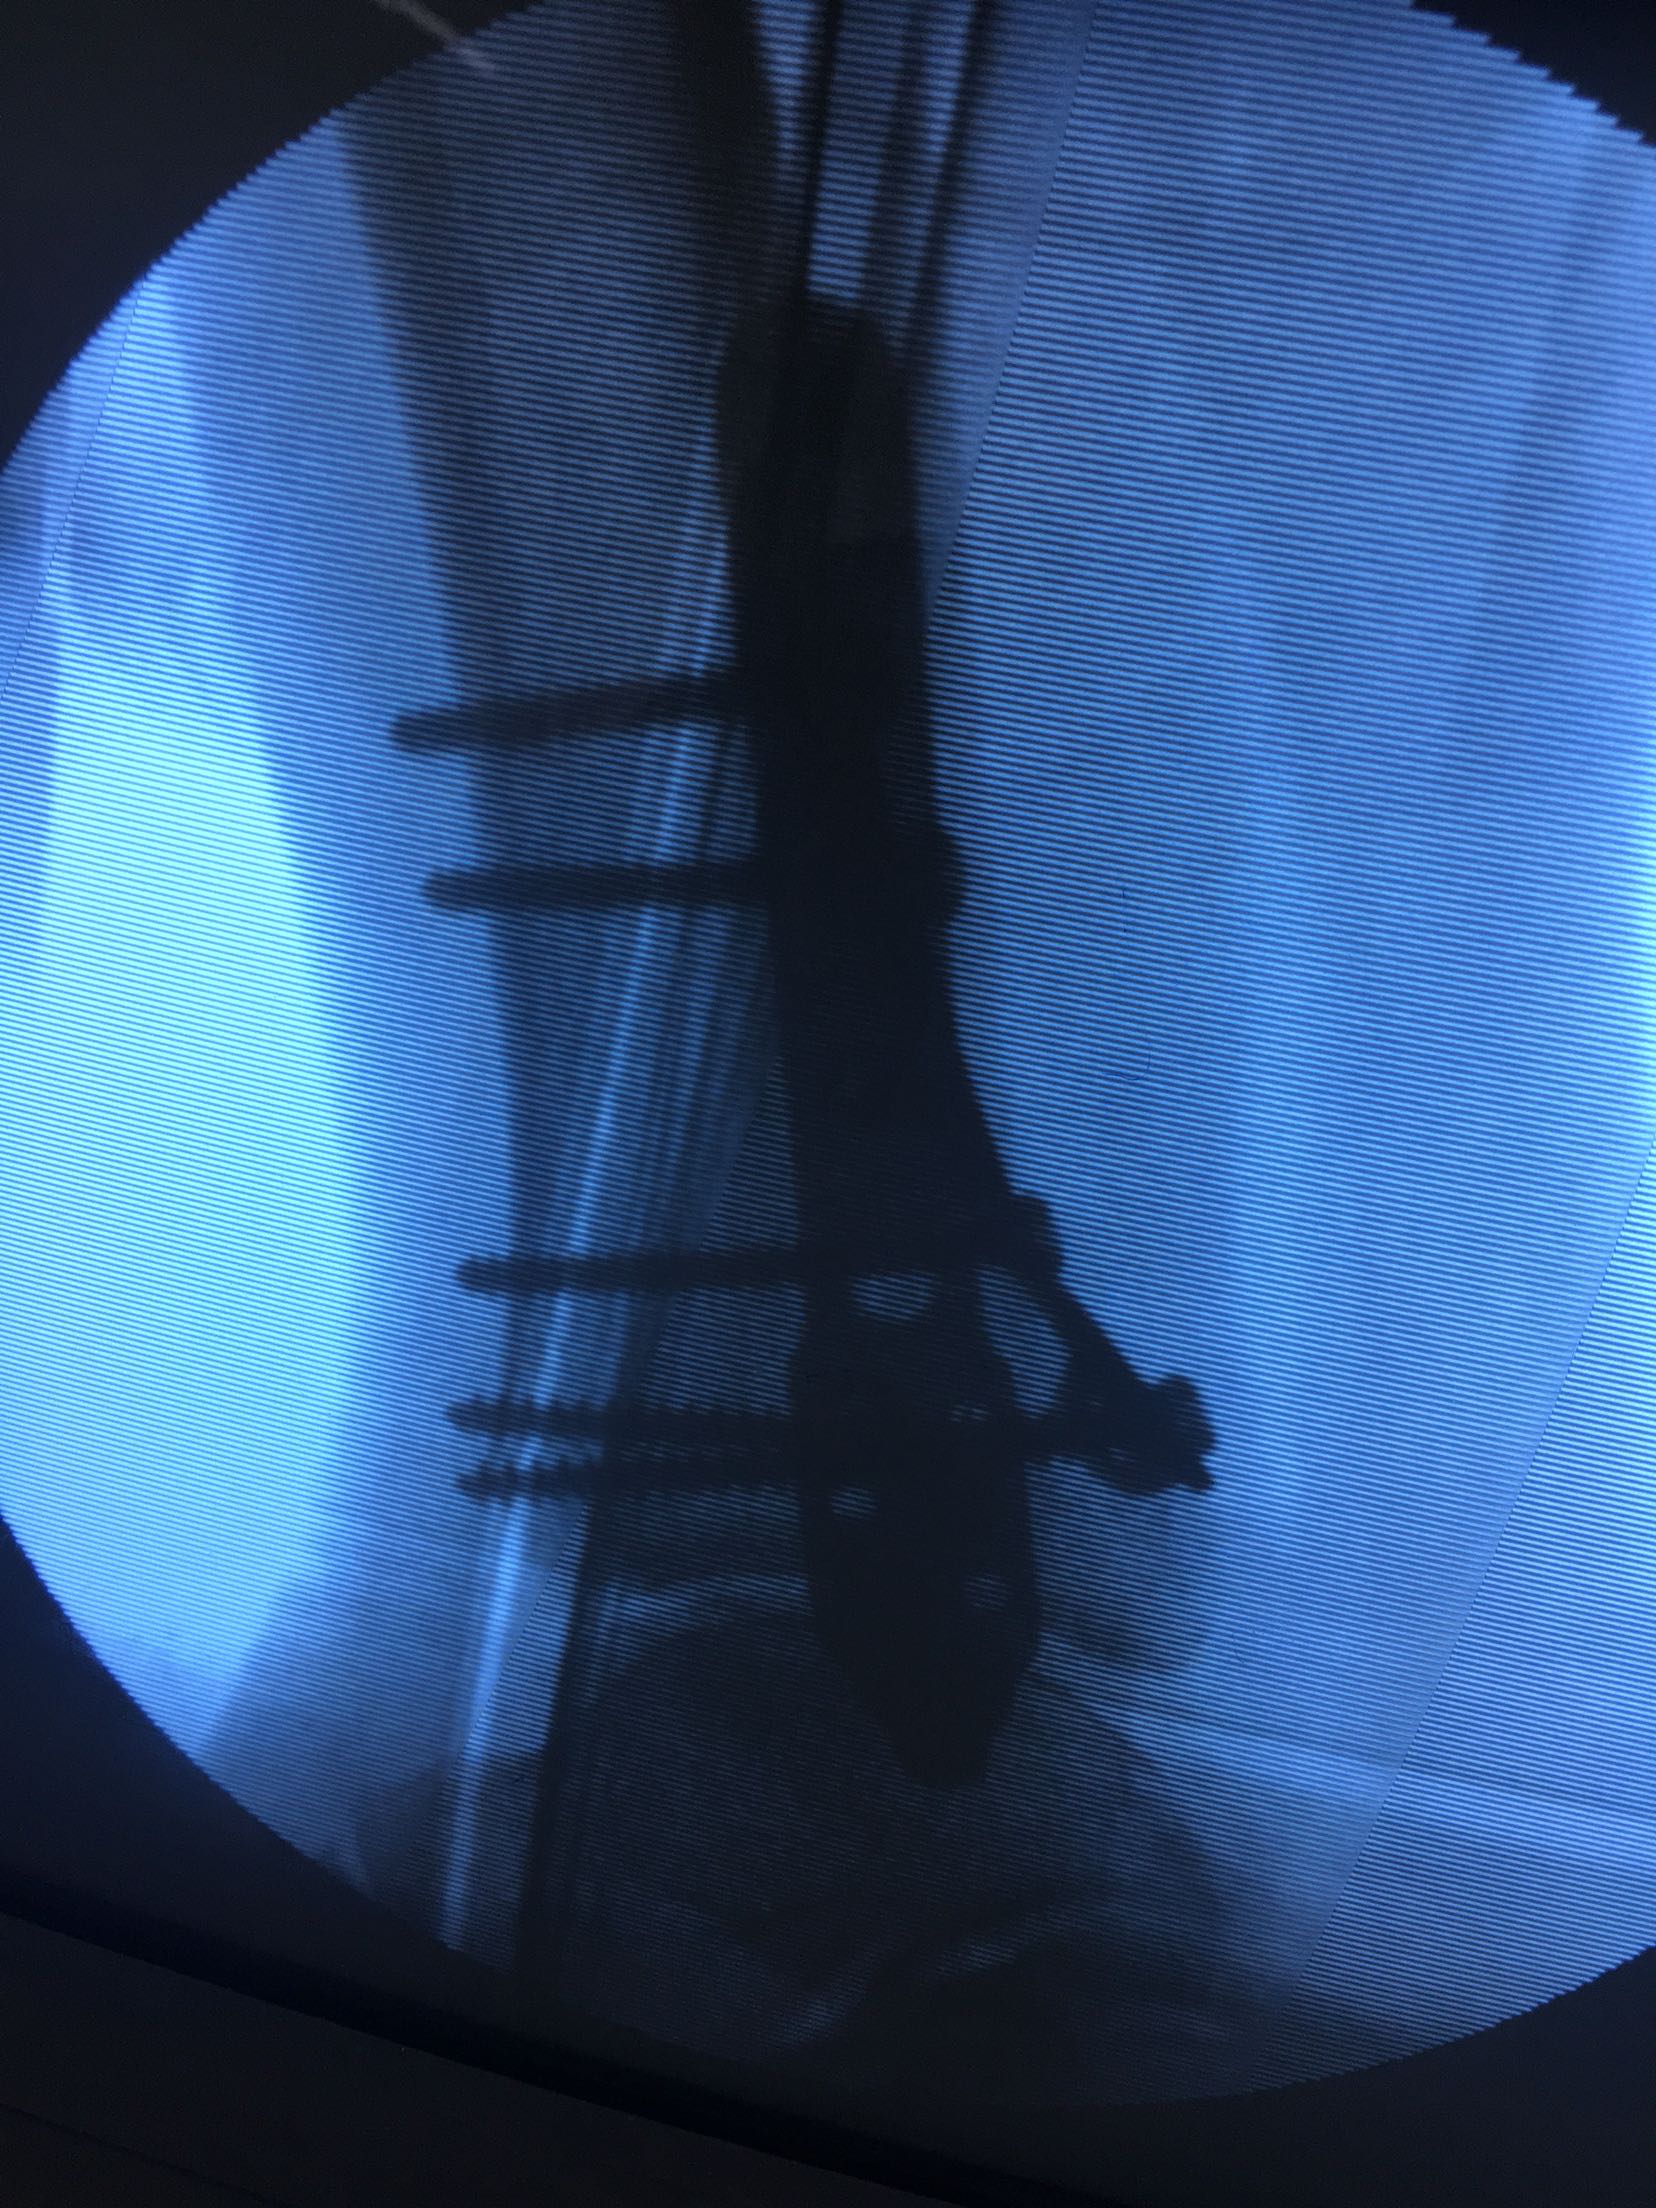

三踝粉碎性骨折(切复内固定)

急诊行跟骨结节牵引,术后一周肿胀消退,在腰麻下行切复内固定术,术后制动抬高,抗炎,消肿等对症处理。